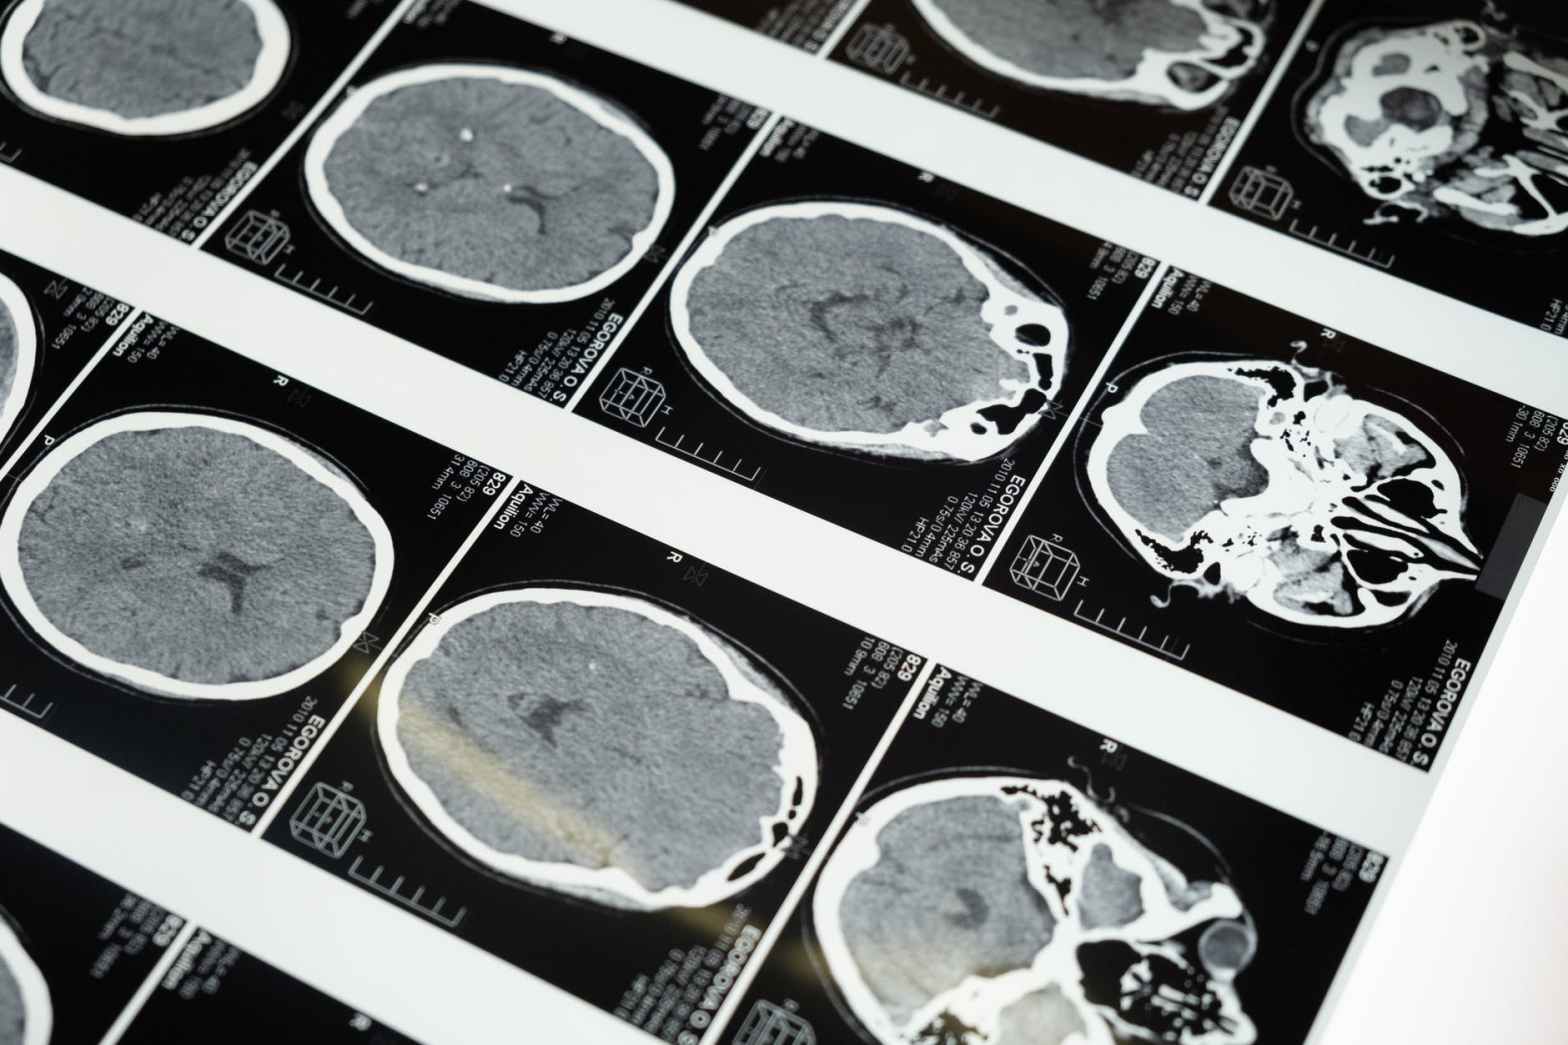

Utilizando el aprendizaje automático, los investigadores han desarrollado un algoritmo que puede diagnosticar con precisión la enfermedad de Alzheimer a partir de una sola resonancia magnética cerebral. El sistema es más preciso que cualquier herramienta de diagnóstico preexistente disponible para los médicos y también puede distinguir la enfermedad en etapa temprana de las etapas másContinue reading “Una sola resonancia magnética promete diagnosticar la enfermedad de Alzheimer en etapa temprana y tardía”